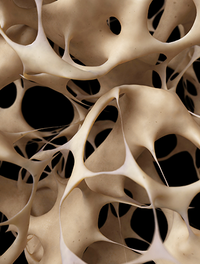

Depuis leur arrivée sur le marché dans le milieu des années 90, les bisphosphonates sont considérés comme le traitement de référence [...]

L’arsenal thérapeutique de l’ostéoporose s’est étoffé ces dernières années. Cependant, en dépit d’avancées majeures, aucun traitement [...]

Inhibiteur du ligand du RANK (RANK L), le dénosumab (anticorps monoclonal entièrement humain), l’empêche d'activer son récepteur, le [...]

Les SERM (pour Selective Estrogen-Receptor Modulators : modulateur sélectif de l’activation des récepteurs aux œstrogènes) sont des [...]

Les fractures ostéoporotiques sont une cause majeure de morbidité et de dépenses de santé. Avec l’arrivée du denosumab (D) s’ouvre [...]